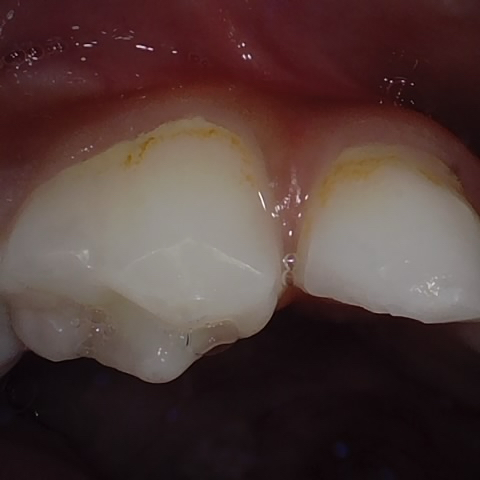

NHD31075

Annotated as "Good"

Original Image Rendering Image